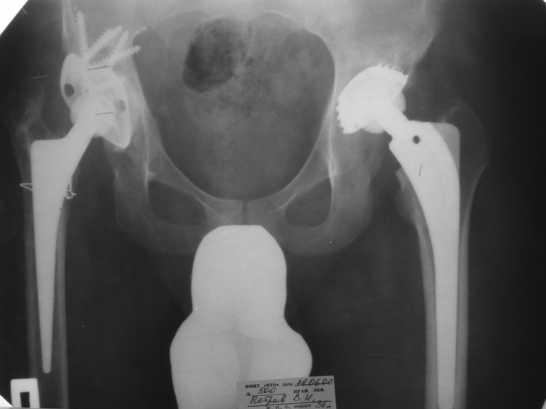

1999г. ревизионное протезирование правого ТБС и вновь инфекционная нестабильность - протез удален.2000 г. установлено кольцо Мюллера и ножка типа Споторно справа (рис. 1).

2003 г. нестабильность тазового компонента (рис. 2) - протез удален.